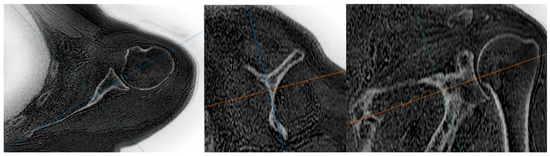

ZTE MRI for Rotator Cuff Tear Arthropathy: Integrated Bone–Muscle Analysis and Its Association with Pseudoparesis

by Engin Türkay Yılmaz, Serkan İbik, Vedat Yaman, Şeyda Betül Fındık, Üstün Aydıngöz and Gazi Huri

J. Clin. Med. 2025, 14(23), 8597; https://doi.org/10.3390/jcm14238597 - 4 Dec 2025

Background/Objectives: Evaluating glenoid changes in rotator cuff tear arthropathy (RCTA) is crucial for preoperative planning. MRI with zero echo time (ZTE) sequence, which produces CT-like images, allows for the assessment of osseous morphology as well as factors contributing to pseudoparesis in RCTA patients. [...] Read more.

Background/Objectives: Evaluating glenoid changes in rotator cuff tear arthropathy (RCTA) is crucial for preoperative planning. MRI with zero echo time (ZTE) sequence, which produces CT-like images, allows for the assessment of osseous morphology as well as factors contributing to pseudoparesis in RCTA patients. Methods: In this retrospective study, using 3T MRI, glenoid version, glenoid vault depth, humeral subluxation index, humeral head medialization, critical shoulder angle, glenoid best-fit circle width, glenoid best-fit circle bone loss ratio (GBLR), and anterior, central, and posterior glenoid bone loss were measured on reformatted 3D ZTE images in 43 shoulders independently by three observers. The same measurements were repeated by one observer after 10 days. Muscle cross-sectional areas were measured. Patients’ active ROMs, American Shoulder and Elbow Surgeons (ASES), and Constant–Murley scores were recorded. Patients unable to perform 90° forward elevation were classified as the pseudoparesis group. Results: Interobserver agreements were good to excellent, except for glenoid vault depth, anterior bone loss, and GBLR. Intraobserver agreements were good to excellent. The pseudoparesis group showed significantly less subscapularis muscle cross-sectional area (p = 0.006). Moderate correlations were found between subscapularis cross-sectional area and forward elevation, abduction, and internal rotation ([r = 0.471, p = 0.001]; [r = 0.447, p = 0.003]; [r = 0.464, p = 0.002], respectively). Moderate negative correlations were found between anterior glenoid loss and forward elevation (r = −0.411, p = 0.006) and abduction (r = −0.475, p = 0.001). Conclusions: MRI with ZTE sequence demonstrated good reliability for assessing osseous morphology in shoulders with RCTA. Glenoid anterior bone loss and loss of subscapularis muscle are both associated with pseudoparesis. Full article